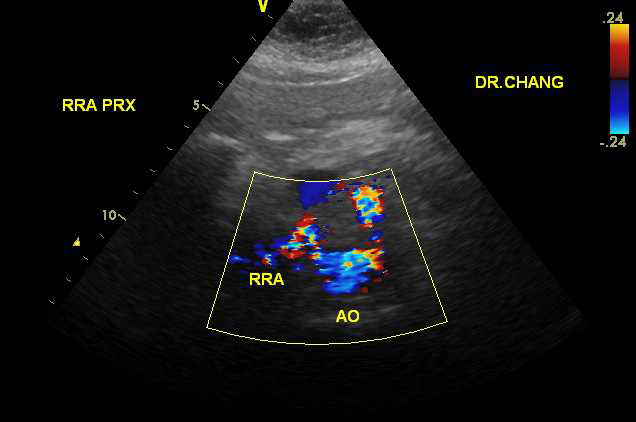

The examination was performed by a registered vascular technologist on a GE Vivid-q ultrasound unit with a M4-S transducer. Gray scale, color and doppler images were obtained from the mid abdominal aorta, the right renal artery and left renal artery. Upon interrogation of the right renal artery, markedly abnormal waveforms and velocities were demonstrated throughout the entire length of the vessel.2 The peak systolic velocity (PSV) was measured at 351cm/sec with an elevated end diastolic velocity of 140cm/sec. The right Renal Aortic Ratio was elevated at 4.3. Of particular interest, color doppler imaging demonstrated a “mosaic” pattern extending from the distal right renal artery into the helium. The left renal artery doppler interrogation was fairly unremarkable with a PSV of 144cm/sec and a Renal Aortic Ratio of 1.78 (Figure 1-3).

Figure 7 Color and Doppler images of RRA FMD.

Figure 8 Color and Doppler images of RRA FMD.

Figure 9 Color and Doppler images of RRA FMD.